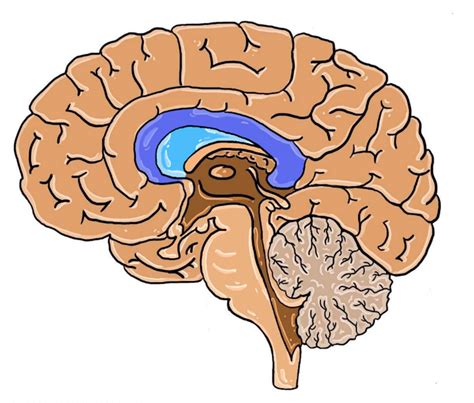

The corpus callosum is a thick band of nerve fibers that connects the left and right hemispheres of the brain. It plays a crucial role in facilitating communication between the two hemispheres, allowing for the integration of information and coordinated functioning. This structure is essential for various cognitive processes, including memory, problem-solving, and sensory perception.

Corpus Callosum Agenesis is a congenital condition, meaning it is present at birth. It can occur as an isolated condition or as part of a broader syndrome. The severity of symptoms can vary widely among individuals, ranging from mild to severe. The condition is often diagnosed through imaging techniques such as magnetic resonance imaging (MRI), which can clearly visualize the absence or underdevelopment of the corpus callosum.